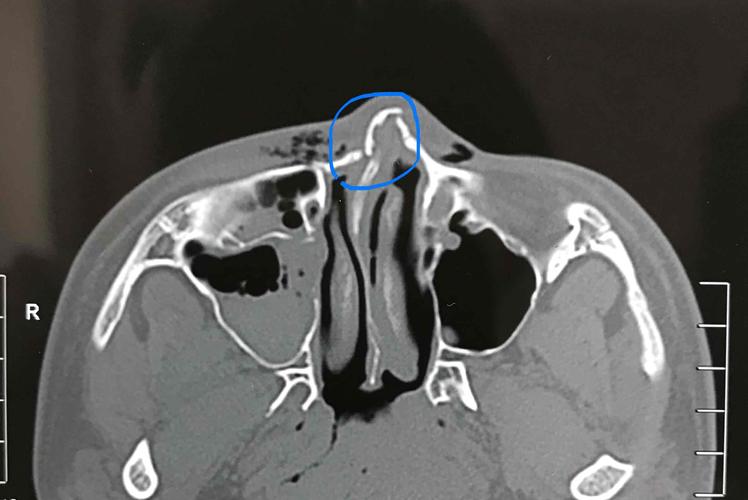

鼻骨骨折片子,鼻骨骨折图片

帮忙看下这个ct片子诊断是鼻骨骨折请问是什么性质的骨折

ct38674:鼻骨骨折吗?

鼻骨骨折图片

鼻骨骨折ct

鼻骨骨折ct图片